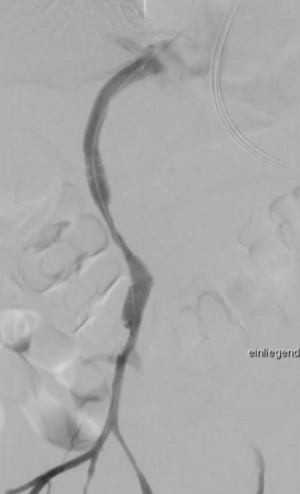

经右侧颈内静脉对肝内门静脉进行穿刺

将 VIATORR CX 型覆膜支架植入体内,以确保能够进入门静脉。 门静脉和肠系膜静脉的血栓清除术 肠系膜静脉中放置带有侧孔的溶栓导管,以处理残留的血栓物质